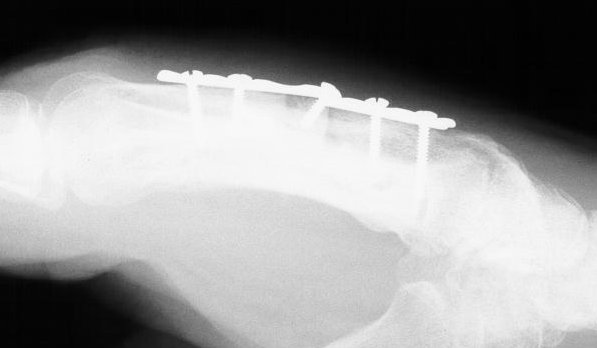

I used the Synthes modular hand set, which has screw intervals different than the small fragment set.

This was the longest plate available, not optimum, but had six cortex purchase on each side of the graft.